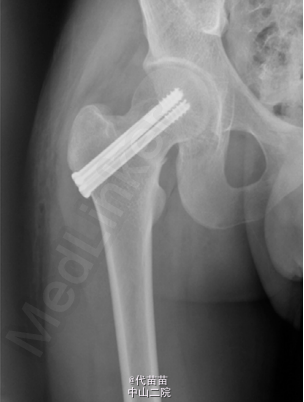

患者男 , 17 岁 , 战士。因右髋部疼痛逐渐加重 1 个月来诊。患者于 2013 年 9 月入伍后开始训练 , 1 个月后无明显诱因出现右髋部疼痛 , 行走及训练时加重 , 休息后能缓解 , 无低热、盗汗 , 无昼轻夜重等现象 , 曾到师医院就诊 , 给予对症治疗 , 后疼痛症状逐渐加重。影响活动 , 不能坚持训练来本院就诊并入院。查体 :一般状况良好 , 心肺腹无异常。右髋部及腹股沟区皮肤无红肿 , 皮温不高 , 无静脉显露 , 右髋后上方压痛 , 无放散 , 右髋部叩击痛阳性 , 右髋关节活动尚好 , 活动时疼痛加重 , 未触及明确包块。血、尿、便化验检查无异常 , 血清碱性磷酸酶 126 U/L。X 线片示 :右股骨颈基底断裂 , 无明显移位 , 局部骨痂形成 ( 见图 1)。诊断:右股骨颈疲劳骨折。入院后完善检查及术前准备, 2 d 后给予行小切口三枚空心螺钉内固定术 ( 见图 2)。术后对症治疗,半个月后拄拐不负重行功能锻炼, 出院后 3 个月复查 X 线片示 :右股骨颈基底部骨小梁及骨皮质连续 , 骨折线消失 , 达到骨性愈合。 应力性骨折又称疲劳性骨折 , 常发生在运动员及新兵训练中 , 此类人员频繁的超负荷训练致骨每天承受反复负荷,以致骨发生局部微损伤 , 如果这种损伤不断积累 , 超过机体修复能力 , 就会产生骨的疲劳性骨折。此类患者往往无明确的外伤史 , 但有大运动量的病史 , 尤其是军人及运动员不能忽视 , 多数患者患侧髋后上部及臀后部疼痛 , 活动时加重 , 休息后缓解 , 部分患者随着病情发展 , 停止运动或休息后仍不能使疼痛缓解 , 查体时 , 患髋后上方及臀部有压痛 ,局部偶有肿胀 , 大粗隆处叩击痛阳性。辅助检查 :DR 及 CR一般可在 1 个月内出现骨膜反应征象 , 大约 3 个月左右由于骨折修复 , 可见有骨痂形成 , 但无法与相关疾病做出鉴别诊断 , CT 的高分辨率扫描 , 能清晰显示骨折线及骨膜增生 , 对平片不能早期确认的病例有较高的诊断价值 , 螺旋 CT 的三维重建可根据需要对高度怀疑的骨组织任意面及任何位置进行重建 , 以此可发现较细的骨折线 , 尤其对于股骨颈及坐骨支等解剖结构复杂区域的疲劳性骨折较适用。MR 其多方位多平面成像 , 敏感性优于 X 线片 , 特别是能早期显示骨折线 ,以及骨折周围软组织 , 髓腔内的水肿和出血。对那些X线片或 CT 扫描有疑问的疲劳骨折病例 , MR 有显著的早期诊断和鉴别诊断价值。 疲劳骨折治疗原则是早发现 , 早治疗 , 可限制原有运动 , 休息为主 , 对极少不稳定或移位的骨折 , 可采取手术固定。此外 , 在训练中 , 应科学施教 , 劳逸结合 , 因每个人的不同体质针对性的制定出训练计划 , 避免同一部位频繁、多次训练。如在训练中出现下肢某部位进行性疼痛 , 应及时来医院诊。